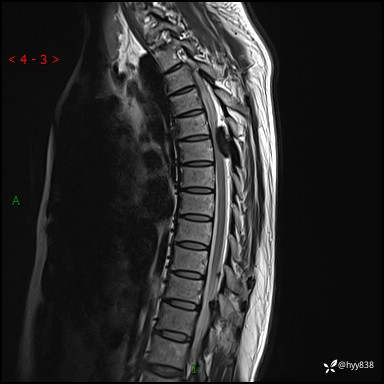

胸椎MRI平扫(sag T1WI+T2WI)